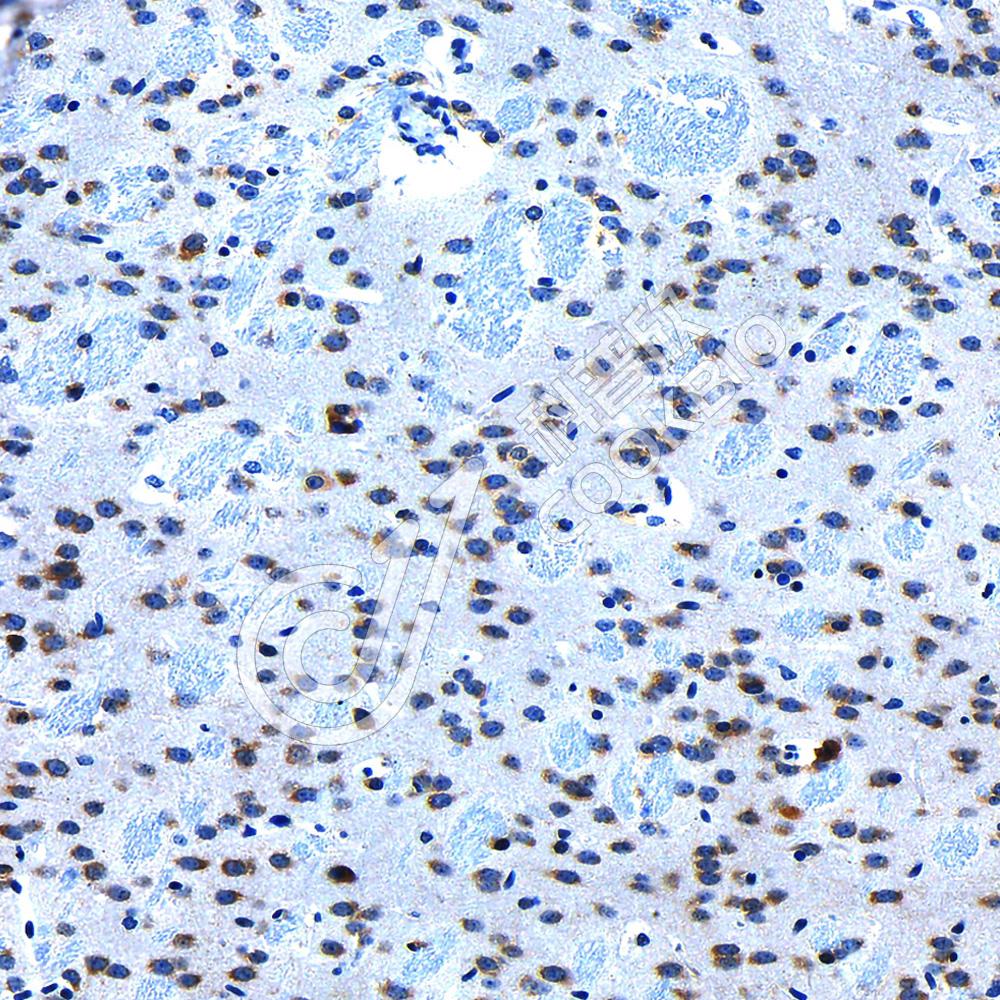

IHC检测Ubiquitin蛋白(货号 K1347100).

样品: 小鼠心, 4%多聚甲醛 (货号KSG1101) 固定12-24小时.

抗原修复: 柠檬酸抗原修复液(干粉, pH 6.0) (KSG1201), 98℃, 20分钟.

—抗: 1: 2300稀释, 4℃ 孵育过夜.

二抗: S-vision免疫组化多聚二抗(山羊抗兔),即用型 (货号KB3906), 室温孵育20分钟.